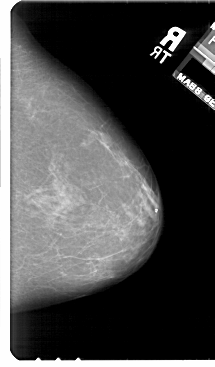

A_1811_1.RIGHT_MLO

RIGHT_CC LINES 5491 PIXELS_PER_LINE 3211 BITS_PER_PIXEL 12 RESOLUTION 43.5 NON_OVERLAY